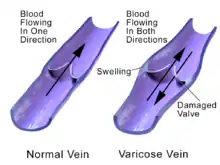

Varicose veins are superficial veins that have become enlarged and twisted.[2][1] Typically they occur just under the skin in the legs.[3] Usually they result in few symptoms but some may experience fullness or pain in the area.[2] Complications may include bleeding or superficial thrombophlebitis.[2][1] When varices occur in the scrotum it is known as a varicocele while those around the anus are known as hemorrhoids.[1] Varicose veins may negatively affect quality of life due to their physical, social and psychological effects.[5]

Often there is no specific cause.[2] Risk factors include obesity, not enough exercise, leg trauma, and a family history of the condition.[3] They also occur more commonly in pregnancy.[3] Occasionally they result from chronic venous insufficiency.[2] The underlying mechanism involves weak or damaged valves in the veins.[1] Diagnosis is typically by examination and may be supported by ultrasound.[2] In contrast spider veins involve the capillaries and are smaller.[1][6]